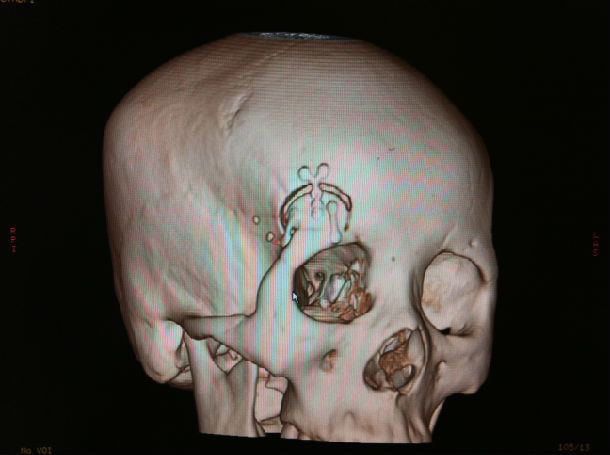

眉弓锁孔入路夹闭前交通动脉瘤新乡市中心医院邢振义